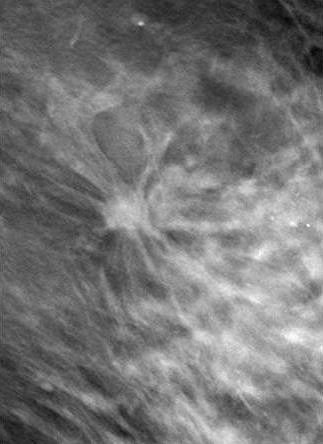

![]() |

| DBT slice image revealed speculated mass (arrow). Biopsy revealed invasive cancer. Image courtesy of Joseph Lo, Ph.D., Duke University Medical Center, Durham, NC, and Siemens Medical Solutions. |